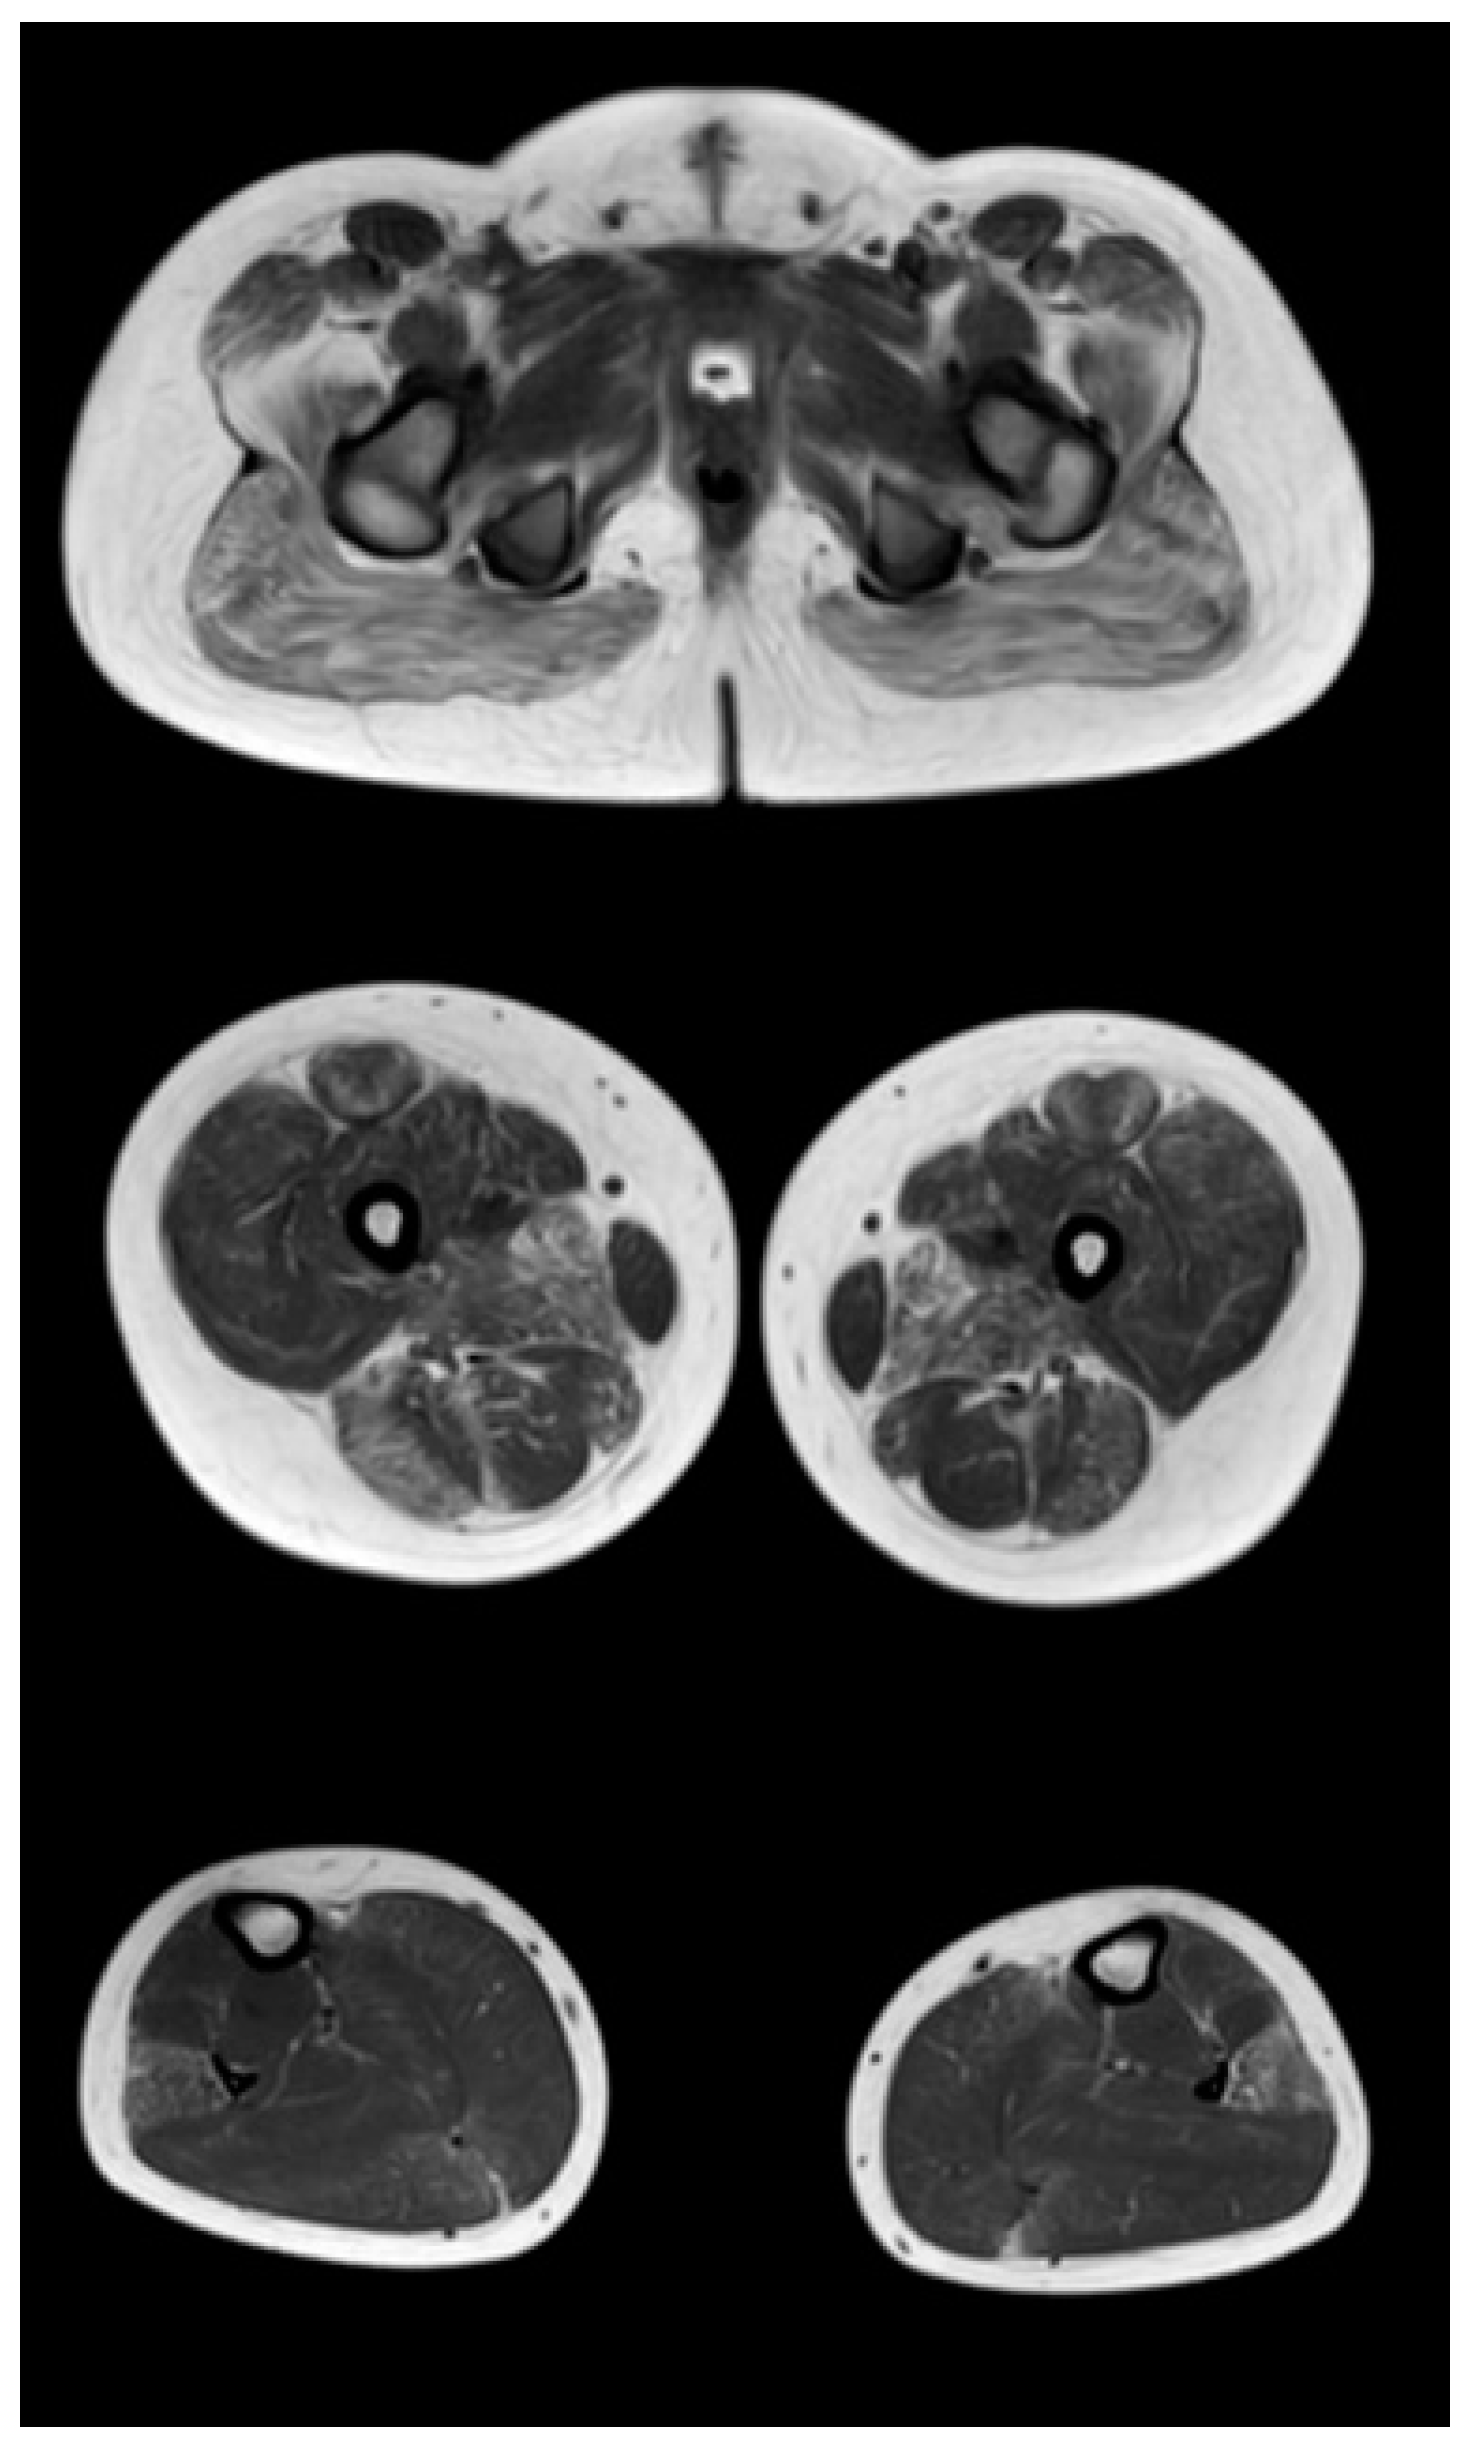

Figure 4.

Pattern of involvement of the muscles of the lower extremities in a patient at the late outpatient stage of the disease (9.4 years). From top to bottom: the pelvic level, the femoral level, and the level of the legs.

At the late outpatient stage, the muscles of the pelvic girdle are characterized by heavy fat substitution of the gluteus maximus and middle muscles (stages 3 and 2b), as well as the muscles straining the fascia lata of the thigh (stage 2b), while the long and short adductor muscles are preserved (Figure 4). In the thighs, progressive fibro-fatty degeneration of the adductor muscles (stage 3), the biceps femoris (stage 2b on the right and stage 2a on the left), semitendinosus, semimembranosus, and quadriceps femoris muscle (stage 2a) is visualized. Thin and sartorius muscles at this stage are characterized by minimal changes or complete preservation (0–1 stages). At the late outpatient stage, the legs are characterized by a pronounced progressive lesion of the long peroneal muscles (stage 3) and of the medial and lateral heads of the gastrocnemius muscles (stage 2a).